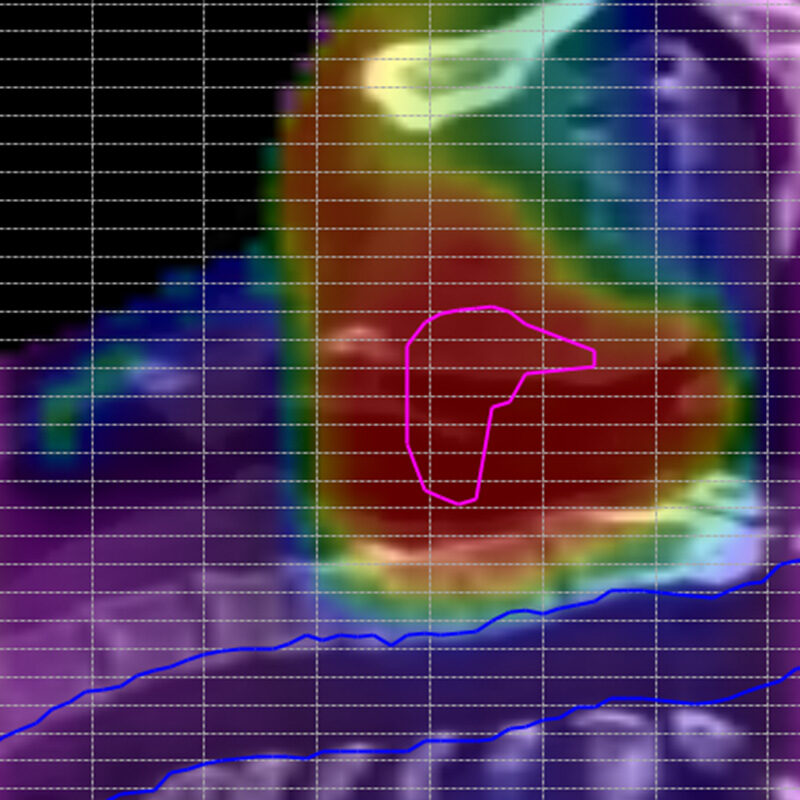

Dose verification in the patient anatomy

With the Delta4DVH Anatomy software option, you can verify and analyze the dose that has been delivered to the patient anatomy. Based on the measurements in the isocentric target region and dose calculation of the dose in the patient anatomy you now have a truly independent verification of the delivered dose.

Analyze the dose delivered to the patient anatomy

Optimization of the angular resolution of the VMAT dose calculation for the Delta 4DVH Anatomy software